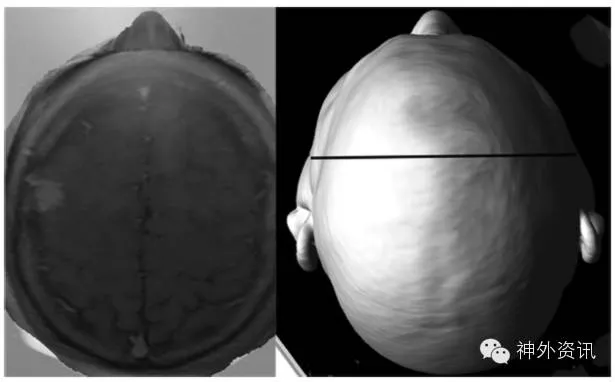

2. 在患者全麻后,作冠状缝和中线标记;然后启动Sina软件,导入轴位图像,助手将指尖放在冠状缝处作为参照点,用于定位头颅的轮廓;采用冠状缝和中线作为解剖标记,将轴位图像与摄像时拍摄的患者头颅图像重叠融合;定位病灶中心,并绘制一条冠状线(图1)。

图1. 左图示如何将轴位影像与患者术中实时头颅图像重合;右图示以病灶为中心绘制冠状线。